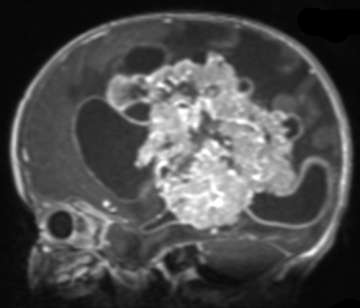

Medulloblastomas

Medical scan shows a brain's blood vessels in blue and red, with a beige tumor highlighted in the center. Click image to enlarge

Medulloblastomas are the most common malignant brain tumors found in children. Between 250 and 500 children under the age of 16 are diagnosed with medulloblastoma each year in the United States, and it accounts for nearly 20% of all childhood brain tumors. Presenting symptoms are usually from obstructive hydrocephalus, and typically include headaches, nausea and vomitting, clumsiness, visual changes, and issues with coordination. Surgery is the first step in treating medulloblastoma, followed by chemotherapy and/or radiation therapy. The survival rates in children depend on the surgeon’s ability to safely and completely remove the tumor, and the sub-type of medulloblastoma. With optimal care, long-term survival rates can be better than 80%.